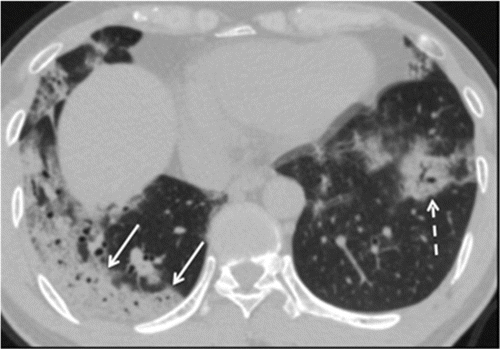

img10666.gif

Figure 3: An axial CT image obtained without intravenous contrast in a 42‐year‐old male in the “late” time group (10 days from symptom onset to this CT) shows bilateral consolidative opacities, with a striking peripheral distribution in the right lower lobe (solid arrows), and with a rounded morphology in the left lower lobe (dashed arrow).